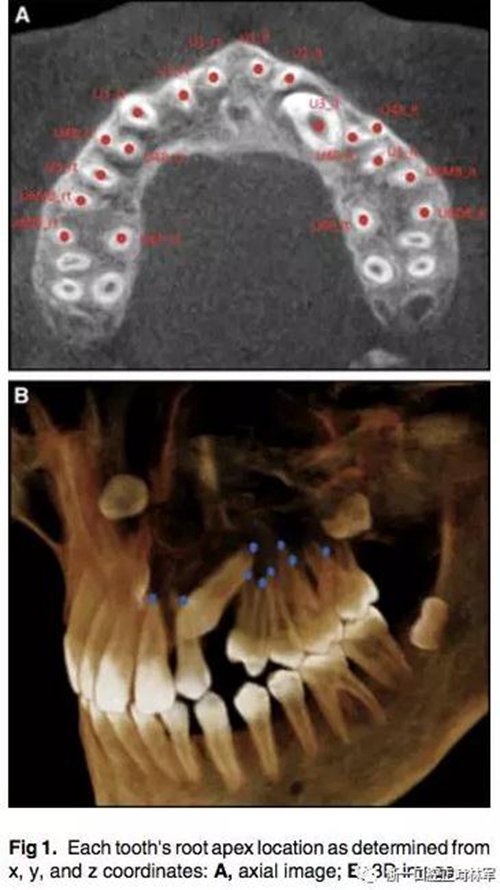

通過(guò)CBCT來(lái)確定尖牙牙根的具體位置,以x,y,z三維坐標(biāo)表示。我們定義在面中線上,鼻根點(diǎn)作為鼻額縫在額骨上的最前點(diǎn),CBCT掃描儀與腭平面水平。我們用3個(gè)標(biāo)志點(diǎn)(前鼻棘點(diǎn),兩側(cè)腭大孔的中心點(diǎn))來(lái)定位腭平面,將鼻根點(diǎn)坐標(biāo)定為(0,0,0),以此確定上頜牙齒根尖點(diǎn)的x,y,z的坐標(biāo)。由于上頜前磨牙和磨牙有2-3個(gè)牙根,因此將多個(gè)牙根的中心點(diǎn)作為根尖點(diǎn)。見(jiàn)Fig1.

為了測(cè)量根尖與牙根弓形的偏移程度,必須先確定牙根的平均位置。然后,測(cè)量每個(gè)牙根與弓形的距離,對(duì)于阻生尖牙,它的牙根平均位置為對(duì)側(cè)非阻生尖牙對(duì)稱得到,測(cè)量阻生尖牙的牙根與對(duì)稱而來(lái)的牙根位置之間的距離。